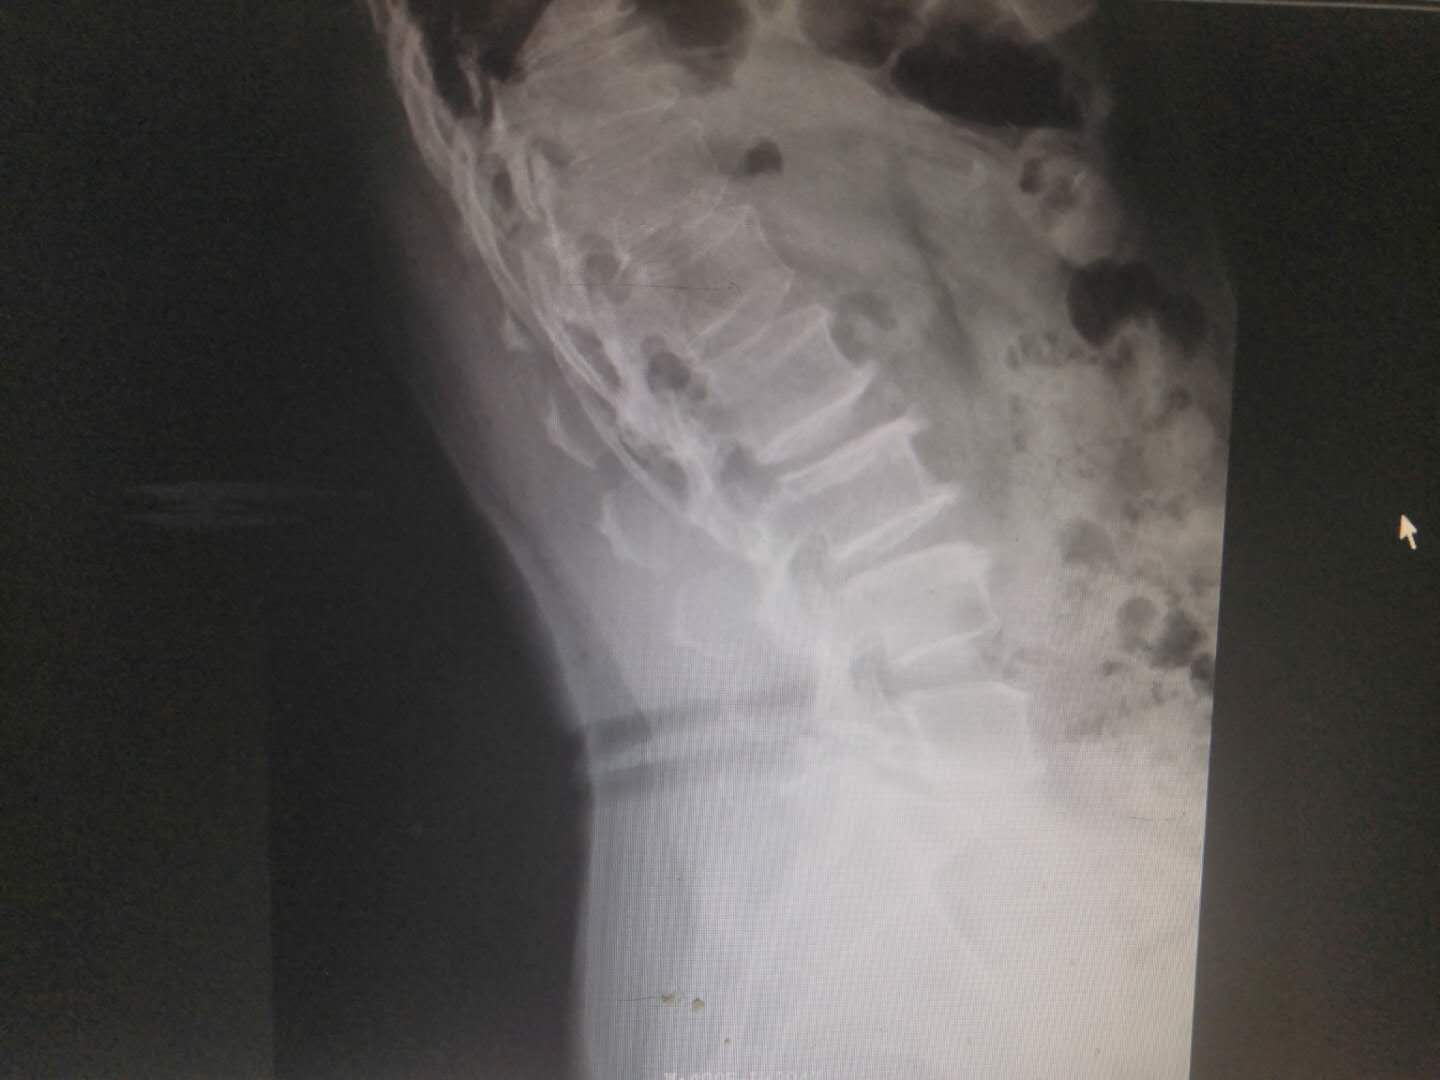

患   者:杨某,女,56岁。

主   诉:因反复腰痛伴右下肢疼痛麻木8年,加重6月,入院治疗。

现病史:缘于8年前开始无明显诱因出现腰部疼痛,呈间歇性胀痛,持续时间数分钟至数小时不等,放射至右下肢,伴右下肢麻木,此后症状反复出现,持续时间数小时至数天不等,劳累后加重,休息后缓解,6月前加重,并出现间歇性跛行,目前行走约200米左右需休息后方能继续行走,在当地医院治疗(药物+理疗)后效果欠佳,现特至我院就诊。

专科检查:颈胸椎各棘突无明显压痛,颈部活动正常,L3-5棘突及椎旁存轻压痛及叩击痛,疼痛无放射,腰部屈伸活动轻度受限,右下肢直腿抬高试验阳性(40度),加强试验阳性,双侧跟臀试验阴性,拾物实验阴性,右侧股四头肌、右足拇背伸肌力约4级,右小腿后、外侧、足背、足底感觉较左侧减退,肢端血运正常。

术前影像资料:

诊       断:

腰椎滑脱症(腰5向前III度)并腰椎管狭窄症。

治疗方案:

入院讨论后予在全麻下行腰4、5、骶1椎弓根螺钉内固定+腰5滑脱复位+腰5/骶1髓核摘除并Cage植入椎间植骨融合术。